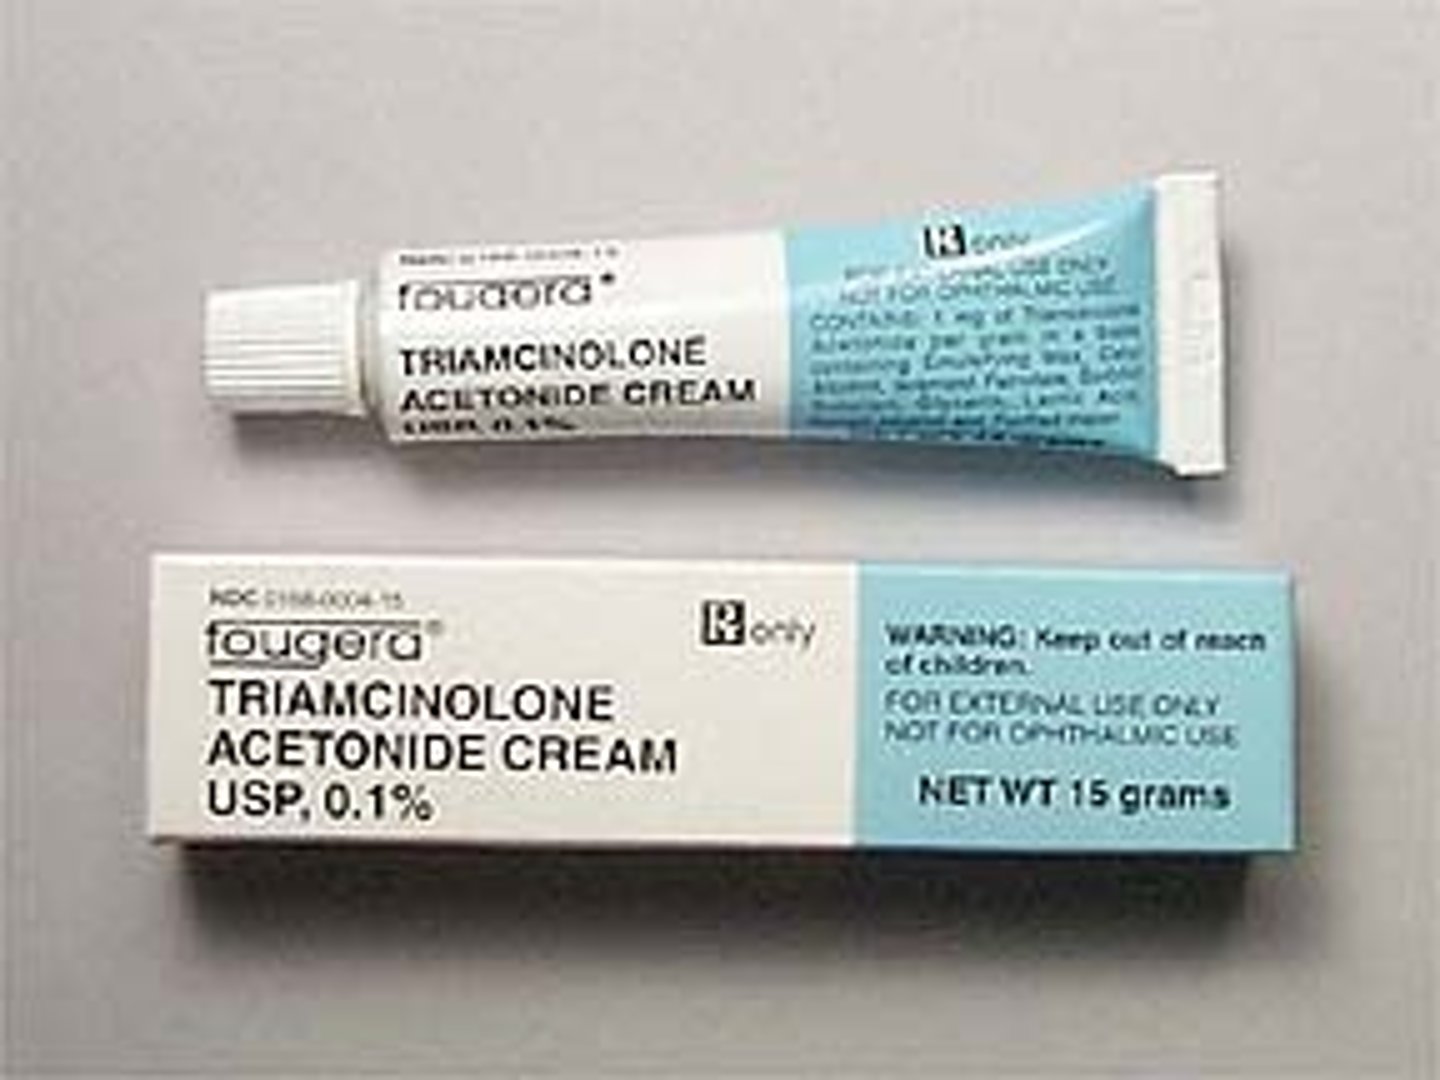

Triamcinolone

Brand: Kenalog

Class: Corticosteroid

Indication: Anti-Inflammatory

Schedule: NCLM